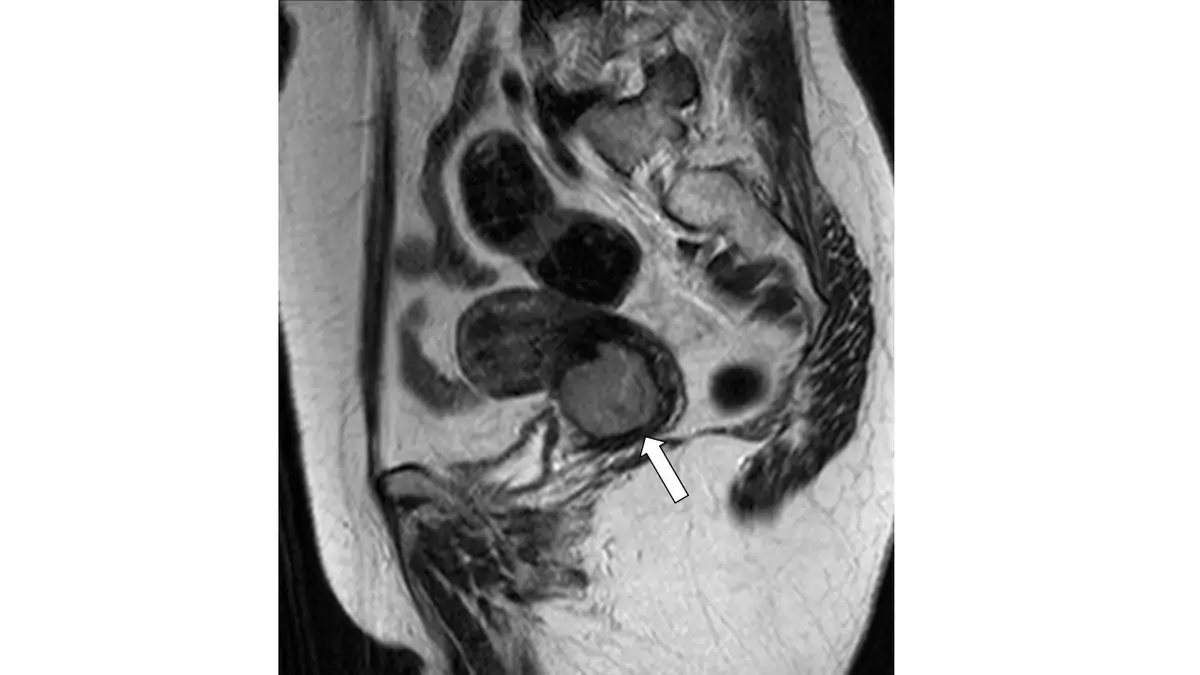

59 歲女性,下腹部磁振造影檢查( T2WI )如圖,有關箭號所指之處,何者敘述最正確?

本圖為骨盆腔矢狀切面 T2WI 影像,呈現以下所見:

子宮體:子宮體內可見多個圓形、界限清楚的低訊號(hypointense)腫塊,分布於子宮前後壁及體部,呈典型子宮肌瘤(uterine leiomyoma)的 T2WI 低訊號特徵。

白色箭號指示處(子宮頸部位):箭號指向子宮頸(cervix)區域,可見一個中等至較高訊號強度(intermediate-to-high signal intensity)的腫塊,破壞了原本正常子宮頸基質(cervical stroma)的低訊號環(hypointense stromal ring)。此腫塊位置明確位於子宮體下方的子宮頸,與體部的多個低訊號肌瘤截然不同,其訊號特徵和位置均符合子宮頸癌的典型 MRI 表現。

正常子宮頸 T2WI 解剖:中央子宮頸內腺體/黏膜呈高訊號,外圍纖維基質呈低訊號環;當子宮頸癌存在時,此低訊號環被中等訊號的腫瘤組織所破壞取代。